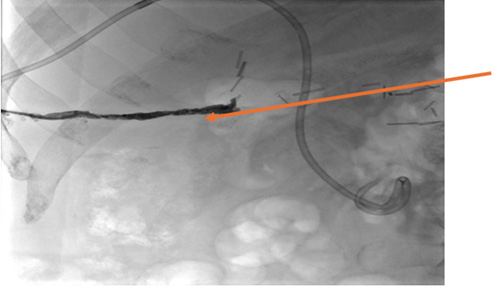

After extensive discussion with IR staff, the decision was made to remove the catheter. First Amplatz wire was advanced to the existing catheter then the catheter was withdrawn over the wire exchange for a JB 1 catheter. The JB 1 catheter was advanced across the fistula and then Successful glue embolization of tract was noted post procedurally (Image 4) without evidence of leakage of enteric contents. A sterile dressing was applied. The patient tolerated the procedure well. For 2 months following embolization, the patient has not experienced cutaneous drainage of bilious or enteric contents.